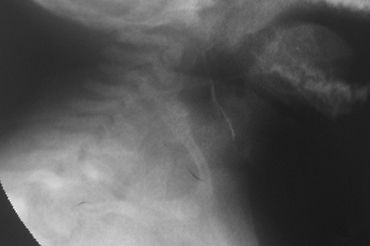

Fistula Branquial